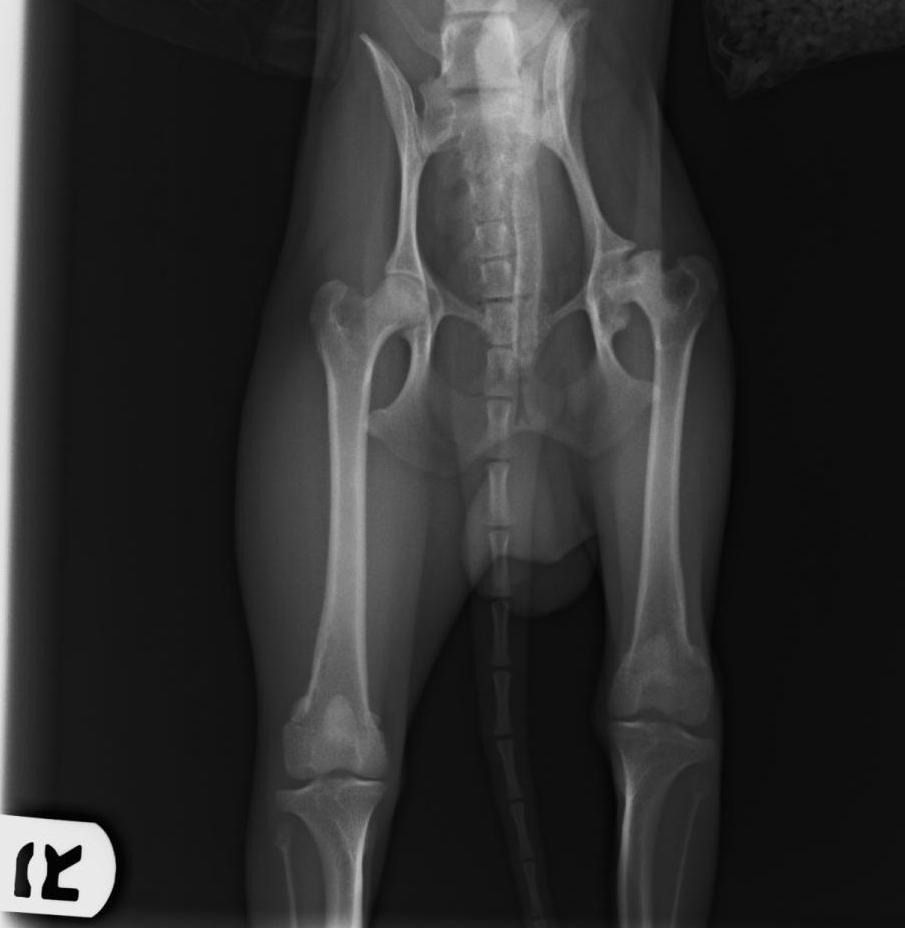

Displasia de cadera

Se trata de una enfermedad hereditaria, que se suele dar en razas como el pastor alemán, labrador, mastín, rottweiler, etc. Suele empezar a dar problemas a partir de los 7-8 meses de edad del cachorro, y es muy importante la detección precoz de la enfermedad.

El tratamiento puede ser

conservador, y si éste no funciona, pensar en un tratamiento quirúrgico. En este caso, cuanto antes hagamos la cirugía, mejor pronóstico va a tener nuestro perro.

Si lo que queremos es prevenir, es muy importante realizar radiografías si son de una raza predispuesta. Además, ofrecemos la posibilidad de realizar un Test Genético para labradores, mediante una muestra de sangre, y nos predice la capacidad de tener y transmitir la enfermedad a la descendencia.